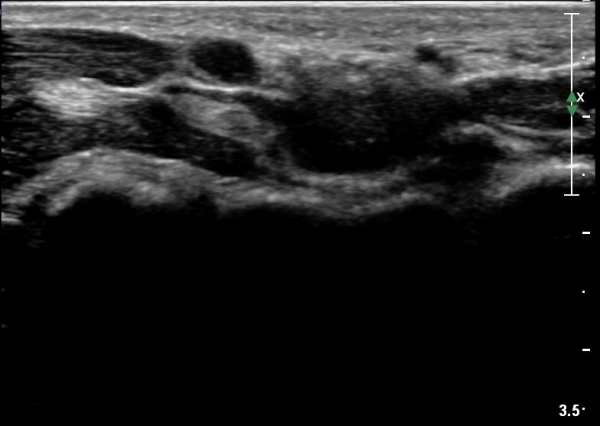

¼Õ¹Ù´Ú ±ÙÀ§ºÎ Ⱦ´Ü¸é°Ë»ç¿¡¼­ Á¤Á߽ŰæÀº ºÎÁ¾ µî ƯÀÌ ¼Ò°ßÀÌ º¸ÀÌÁö ¾ÊÀ¸³ª

¹«Áö±Ù °æ°èºÎ ̫̿¿¡ Àú¿¡ÄÚ Á¾¾çÀÌ °üÂûµÈ´Ù(»çÁø 4, 5).

¼Õ¹Ù´Ú ±ÙÀ§ºÎ¾Æ·¡·Î ŽÃËÀÚ¸¦ À̵¿ÇÏ´Ï Á¾¾çÀÌ ´õ Ä¿Áö°í Á¤Á߽ŰæÀÇ ¹«Áö±Ù °¡Áö°¡ °üÂûµÈ´Ù.(»çÁø 6).

ŽÃËÀÚ¸¦ Á¶±Ý ´õ ¸»´ÜÀ¸·Î À̵¿ÇÏ´Ï Á¾¾çÀÌ ´õ Ä¿Áö°í Á¤Á߽ŰæÀÇ ¹«Áö±Ù °¡ÁöÀÇ ¾Ð¹ÚÀÌ

°üÂûµÈ´Ù.(»çÁø 7, 8).

Á¾¾çÀÇ Á¾´Ü¸é°Ë»ç¿¡¼­ Á¾¾ç°ú À̾îÁö´Â Àú¿¡ÄÚ ¶ì°¡ °üÂûµÇ´Âµ¥ °üÂûµÇ´Â ¾ç»óÀ¸·Î º¼ ¶§

½Å°æÁ¾À¸·Î ÃßÁ¤µÈ´Ù(»çÁø 9, 10).